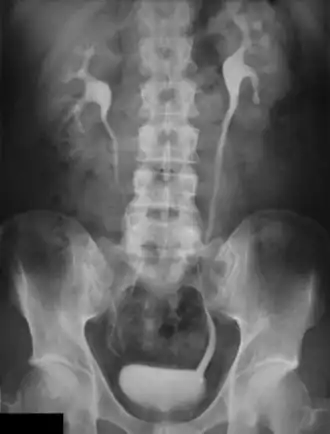

Urografia

Urografia – badanie radiologiczne mające na celu uwidocznienie nerek i dróg moczowych oraz ocenę czynności nerek.

Badanie polega na dożylnym podaniu środków kontrastowych (np. Uropolinum, bądź nowocześniejszych i bezpieczniejszych niejonowych środków kontrastujących) i następowym wykonaniu zdjęć radiologicznych jamy brzusznej.

Pierwsze zdjęcie wykonuje się jednak jeszcze przed podaniem kontrastu (zwykłe zdjęcie przeglądowe jamy brzusznej) i następne 7 minut po podaniu kontrastu, a następne po upływie dalszych 14 i 21 min.